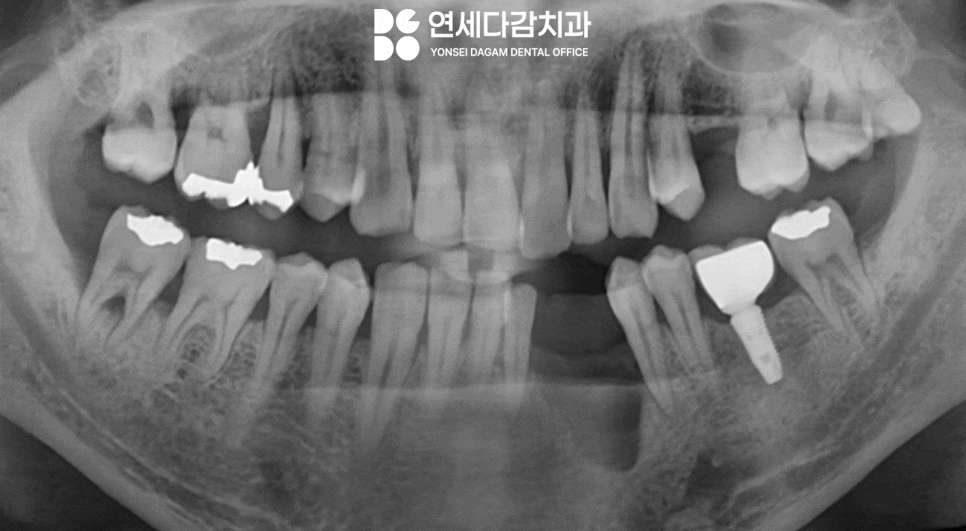

우선 사진을 보면 앞니 부위에

심한 골결손이 눈에 띕니다.

이처럼 심한 골소실로 다른 곳에서는

뼈가 없으니 브릿지 치료를

진단받은 스토리가 있습니다.

그 외에도 어금니 부위에도

결손된 곳이 존재했으며,

오른쪽 아래 끝에 어금니는

치아 상태가 좋지 않아

보존할 수 없는 hopeless 상태였습니다.